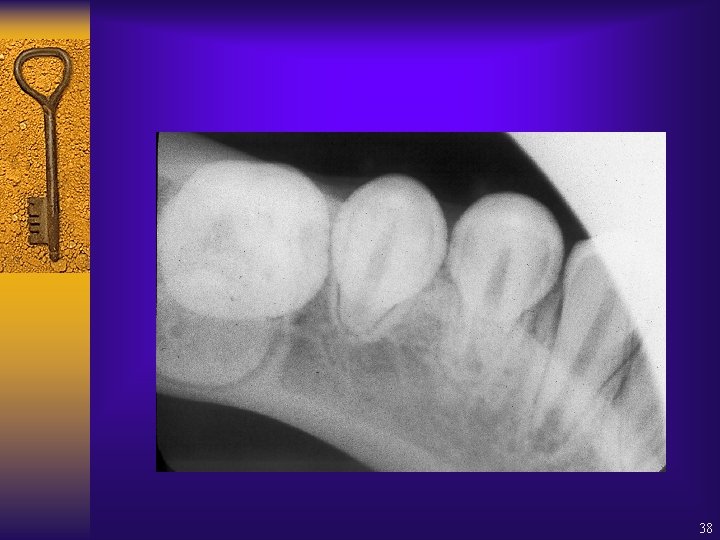

Supernumerary tooth – where is it? 37

38